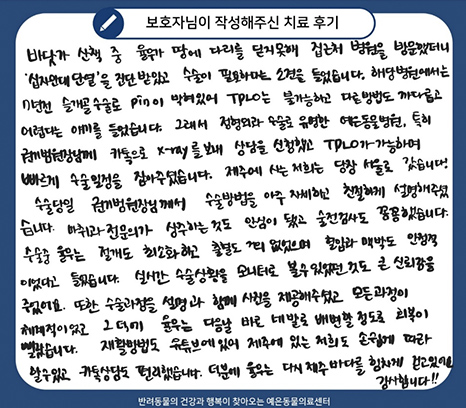

제주도에서 수술 받으러 온 율무 십자인대 TPLO 후기

바닷가 산책 중 율무가 땅에 다리를 딛지 못해 집근처 병원을 방문했더니 ‘십자인대 단열’을 진단 받았고 수술이

필요하다는 소견을 들었습니다. 해당 병원에서는 7년 전 슬개골 수술로 pin이 박혀있어 TPLO는 불가능하고

다른 방법도 까다롭고 어렵다는 얘기를 들었습니다.

그래서 정형외과 수술로 유명한 예은동물의료센터, 특히 권기범 원장님께 카톡으로 x-ray를 보내 상담을 신청했고

TPLO가 가능하며 빠르게 수술일정을 잡아주셨습니다. 제주에 사는 저희는 당장 서울로 갔습니다.

수술당일 권기범 원장님께서 수술방법을 아주 자세하고 친절하게 설명해주셨습니다.

마취과 전문의가 상주하는 것도 안심이 됐고 수술전 검사도 꼼꼼했습니다.

수술 중 율무는 절개도 최소화했고 출혈도 거의 없었으며 혈압과 맥박도 안정적이었다고 들었습니다.

실시간 수술상황을 모니터로 볼 수 있었던 것도 큰 신뢰감을 주었어요. 또한 수술과정을 설명과 함께 사진을 제공

해주셨고 모든 과정이 체계적이었고 그 덕에 율무는 다음날 바로 네발로 배변할 정도로 회복이 빨랐습니다.

재활방법도 유튜브에 있어 제주에 있는 저희도 손쉽게 따라 할 수 있고 카톡상담도 편리했습니다.

덕분에 율무는 다시 제주 바다를 힘차게 걷고 있어요. 감사합니다.